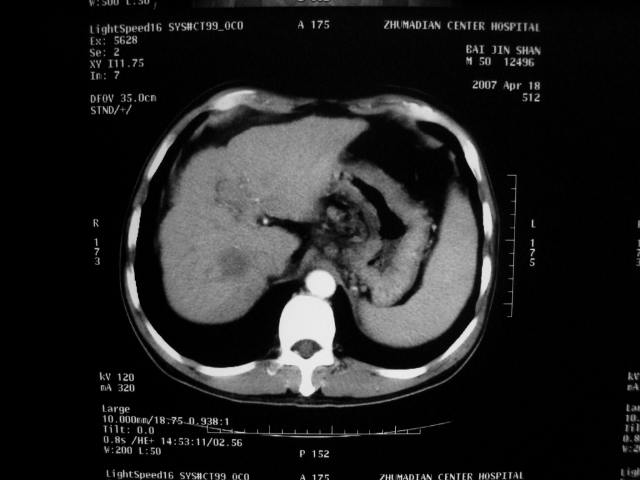

标题: CT7751:病人,50岁,肝硬化多年,行CT三期扫描 [打印本页]

标题: CT7751:病人,50岁,肝硬化多年,行CT三期扫描

动脉期病灶见轻度强化,考虑肝癌可能性大。

动脉期轻度强化 考虑 肝右叶小肝癌可能性大

肝硬化 脾大 胃底静脉曲张 肝癌 门腔间淋巴结肿大

1、肝右叶低密度灶考虑肝癌

2、肝硬化

肝硬化、脾大,静脉曲张,肝右叶低密度灶,增强无明显强化,还是考虑肝癌可能性大,建议结合afp检查。

考虑肝硬化,脾大,静脉曲张,肝右叶低密度灶,右肝癌可能性大。

肝癌分为肝细胞性和胆管细胞性,从强化表现来看,确切地说应是胆管细胞癌.